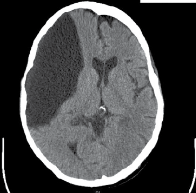

Man with a porencephalic cyst was admitted to the family medicine inpatient service for abdominal pain and hematochezia.